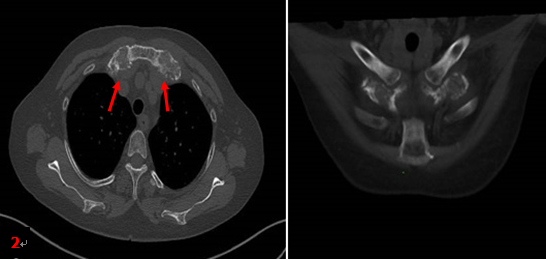

患者同期胸部CT檢查所見(圖2箭):雙側(cè)第1前肋對(duì)稱性肥厚、膨大、骨質(zhì)硬化,未見明顯軟組織腫塊。